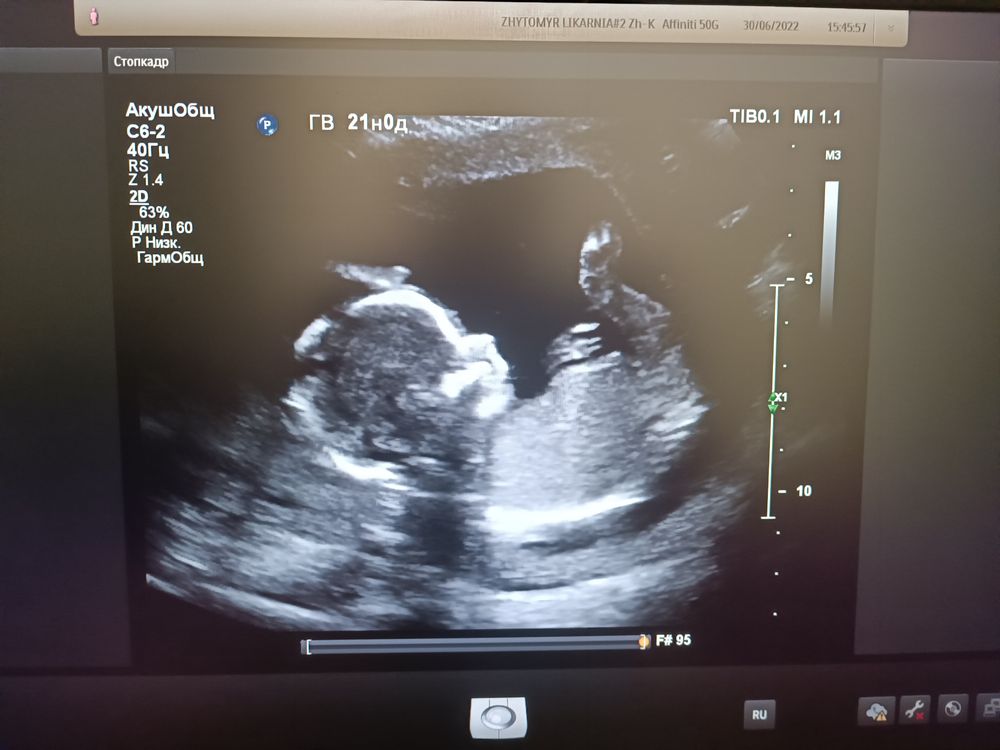

Девочки, я обещала обязательно сообщить результаты гендер-пати,вчера провели,на руках фото ещё нету,но как оказалось мы ждём второго мальчика))) Я буду дважды свекровью! Для тех, кто думает проводить или не проводить такое мероприятие могу сказать,что оно однозначно того стоит)) Эмоции били через край! Так что,если кому-то наши фото помогут в дальнейшем определении пола-буду рада помочь)))